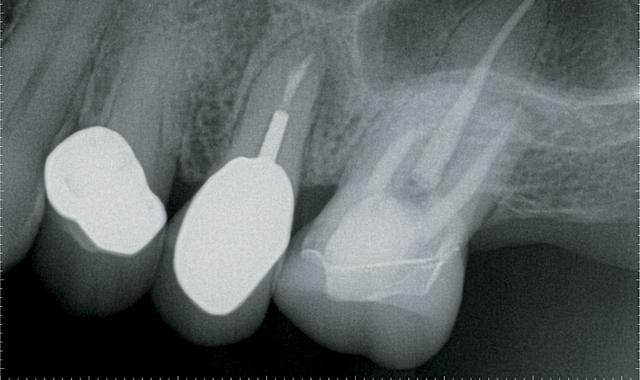

Fig. 1

Step 1: The patient presented with a cracked root on #13 (Fig. 1). The treatment plan options were extraction of #13 with bone grafting and implant placement or extraction of #13 with a fixed bridge for #12-14. A Galileos® CBCT scan showed that primary stability of an implant placed at the time of extraction could not be achieved. The tooth would need to be extracted with socket grafting, heal for three to four months and then be followed by implant placement.

The patient found the first treatment option to be unacceptable. Teeth #12 and #14 already had crowns, so replacing these crowns with a fixed bridge would not sacrifice healthy teeth. Understanding all of the benefits and risks, the patient opted for the second option of a fixed bridge.